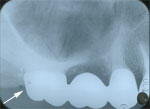

1.抜歯前

第二大臼歯(×印)は、むし歯で、根が少し残るのみ。 抜歯

とする。

親知らず(一番左の歯)が、歯ぐきの中に,埋もれている。

歯ぐきを少し切り、出てきやすくした。

第一大臼歯(赤矢印))は深いむし歯(髄床底に及ぶ)で、本

来なら抜歯だが、あまり持たないこととを覚悟で、根の治療

中。この後、歯冠修復完了。親知らずが移動してくるまで

の、時間稼ぎが目的。 |